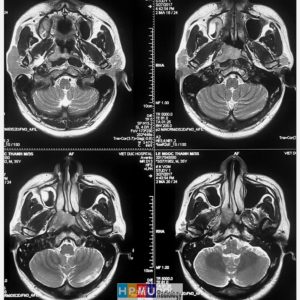

U dây VIII

Lượt xem: 162» 02-03-2019 -

U dây VIII

Lượt xem: 132» 24-11-2018 -

U dây VIII

Lượt xem: 130» 24-11-2018 -

U dây VIII

Lượt xem: 153» 24-11-2018 -

U dây VIII

Lượt xem: 147» 24-11-2018 -

U dây VIII

Lượt xem: 117» 24-11-2018 -

U dây VIII

Lượt xem: 149» 24-11-2018 -

U dây VIII

Lượt xem: 143» 24-11-2018 -

U dây VIII

Lượt xem: 158» 24-11-2018